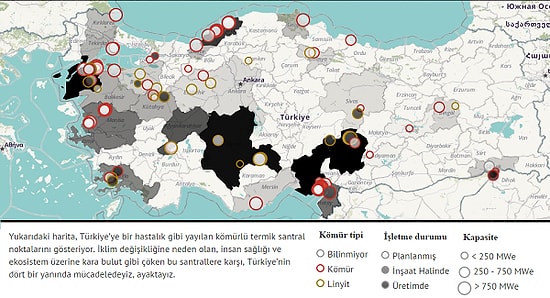

'Kara Atlas' Türkiye’nin Yeni Kanser Haritası mı Olacak?

Greenpeace, 4 Şubat Dünya Kanser Günü nedeniyle yaptığı açıklamada, kansere neden olan en önemli etmenlerden hava kirliliğine ve hava kirliliğinin en önemli nedenlerinden kömürlü termik santrallere dikkat çekti.Türkiye’de planlanan kömürlü termik santraller haritasının, Türkiye’nin kanser haritası olabileceği konusunda uyaran Greenpeace, Sağlık Bakanlığı’nı kömürlü termik santrallerle ilgili harekete geçmeye çağırdı.2013 yılında Dünya Sağlık Örgütü, hava kirliliği ve özellikle gözle görülemeyen parçacık maddelerin başta akciğer ve mesane kanseri olmak üzere pek çok kanser çeşidine sebep olduğunu açıkladı. Havadaki kirliliğin sebepleri arasında sağlık için en tehlikeli olanı, PM 2,5 adlı, saç telinden bile küçük olan ince parçacık maddeler. Her gün tonlarca kömürün yakıldığı kömürlü termik santraller de, kansere yol açan bu sessiz katillerin en önemli sebepleri arasında.Türkiye’de zaten var olan santraller ve mevcut hava kirliliği nedeniyle şu anda pek çok kent zehir soluyor. Buna rağmen 80 yeni kömürlü termik santral planı var ve bu planlarla Türkiye, dünyanın en büyük 4. kömür tehdidi konumunda. Çevre ve Şehircilik Bakanlığı’nın verilerine göre, Türkiye’de 64 ilde trafik, endüstri, yüksek hava kirliliği potansiyeli bulunuyor. Ayrıca bir de bu santraller yapılırsa bacalarından çıkacak olan sessiz katillerin kanser yapacağı resmen ispatlanmış iken, Sağlık Bakanlığı bu santrallere izin verilirken nerede diye soruyoruz?Bu santrallerin yapılacağı yerlere izin verilirken o bölgede kaç tane kanser hastası olduğu ve santraller yapılırsa bu sayının ne kadar artacağının araştırılması gerekiyor. İnsanların temiz hava hakkı ellerinden alındıktan sonra, erken tanı, teşhis ve tedavi ile kanserle savaşıyoruz demek gerçekçi ve yeterli değil. Bu nedenle Sağlık Bakanlığı’nı, hava kirliliğine neden olan kömürlü termik santrallerle ilgili acilen harekete geçmeye çağırıyoruz. Sağlık Bakanlığı halkın sağlığını korumak için izin süreçlerinde aktif rol almazsa, planlanan santralleri gösteren ‘Kara Atlas’ın Türkiye’nin yeni kanser haritası olması kaçınılmaz.